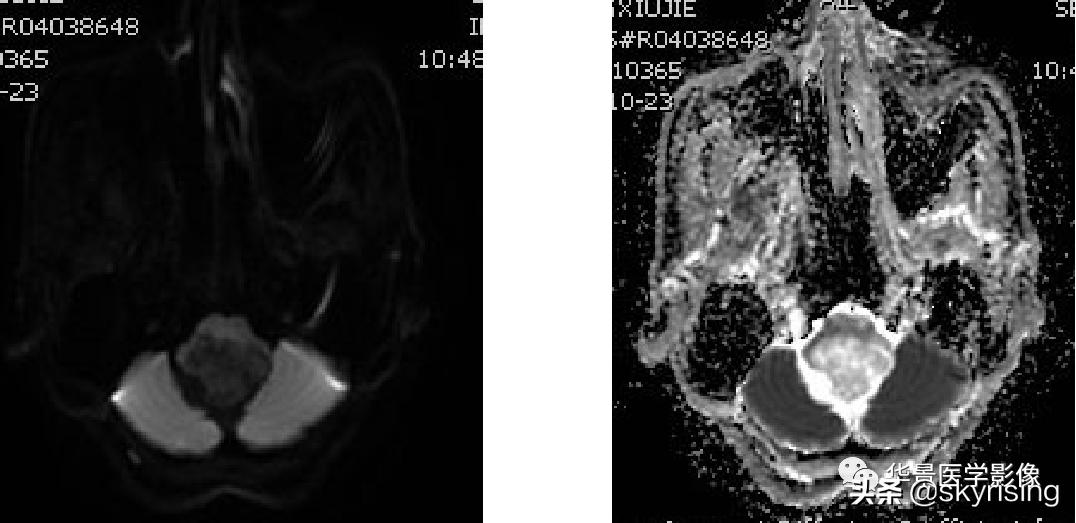

以下依次为T2WI、FLAIR、T1WI、增强、DWI及ADC:

上图白色箭头:小脑延髓池内延髓背侧不规则形团块影,不均长T2信号,FLAIR条片样信号减低,提示水分子含量高。

蓝色箭头:注意病灶与延髓边界不清,不除外来源或侵及延髓。

黄色箭头:右侧细小流空血管信号;左侧较粗大贴边流空信号血管影。

上图白色箭头:病灶呈DWI低信号,ADC高信号,信号欠均,提示弥散不受限。